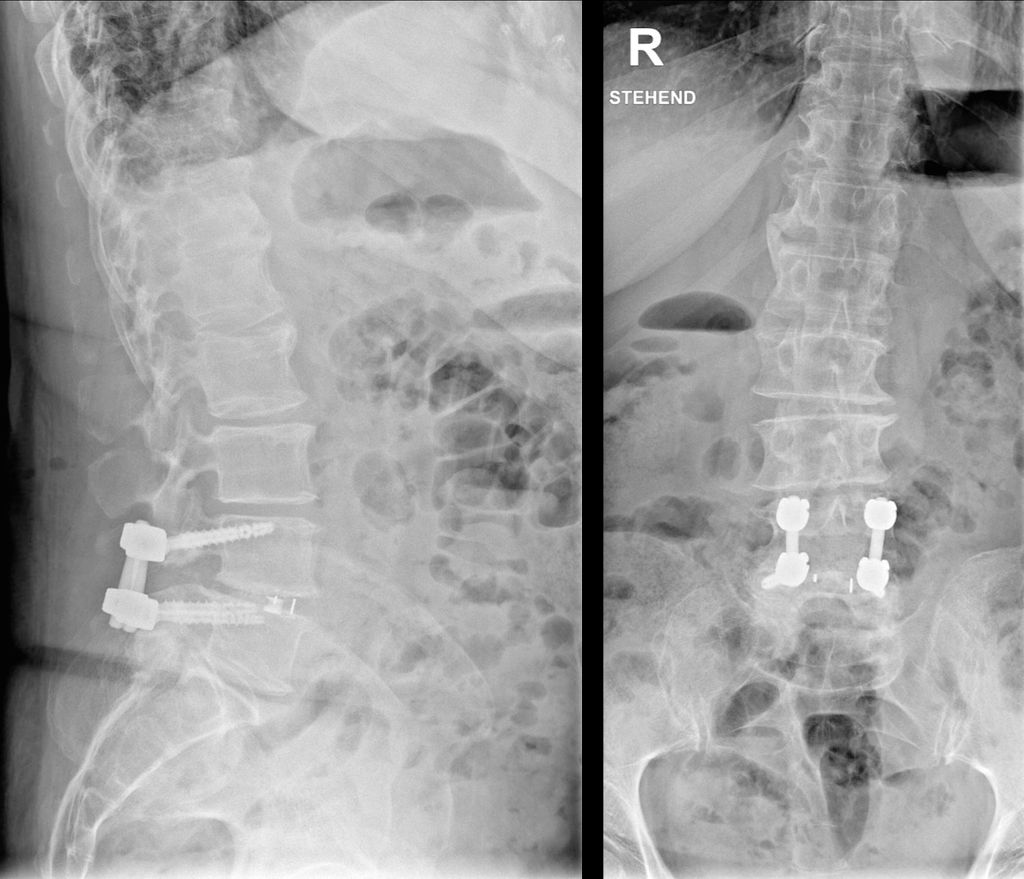

Durch den reduzierten Knochenumbau bei osteoporotischen Patient:innen kommt es auch zu einer verlangsamten knöchernen Fusion, wodurch nicht nur die Risiken für Schraubenlockerungen, sondern auch für Cage-Sinterung (Abb. 2) und Anschlussfrakturen erhöht sind.4, 21 Ein klarer Vorteil für ein bestimmtes Cage-Material dürfte nicht vorliegen. Cages aus Polyetheretherketon (PEEK) oder 3D-Druck versuchen, das Elastizitätsmodell des Wirbelkörpers zu spiegeln. Manche Studien deuten darauf hin, dass reine Titanimplantate eine höhere Sinterungsrate aufweisen als Implantate aus PEEK oder 3D-Druck.25 Viel mehr scheint die Implantatpositionierung und -größe eine Rolle zu spielen. Je mehr Kontakt zur Endplatte besteht, d.h., je größer das Implantat ist und je satter es anliegt, desto eher werden Druckspitzen vermieden und damit das Risiko für Sinterung reduziert.26

Abb. 2: Erhöhtes Risiko für Cage-Sinterung und Anschlussfrakturen durch reduzierten Knochenumbau